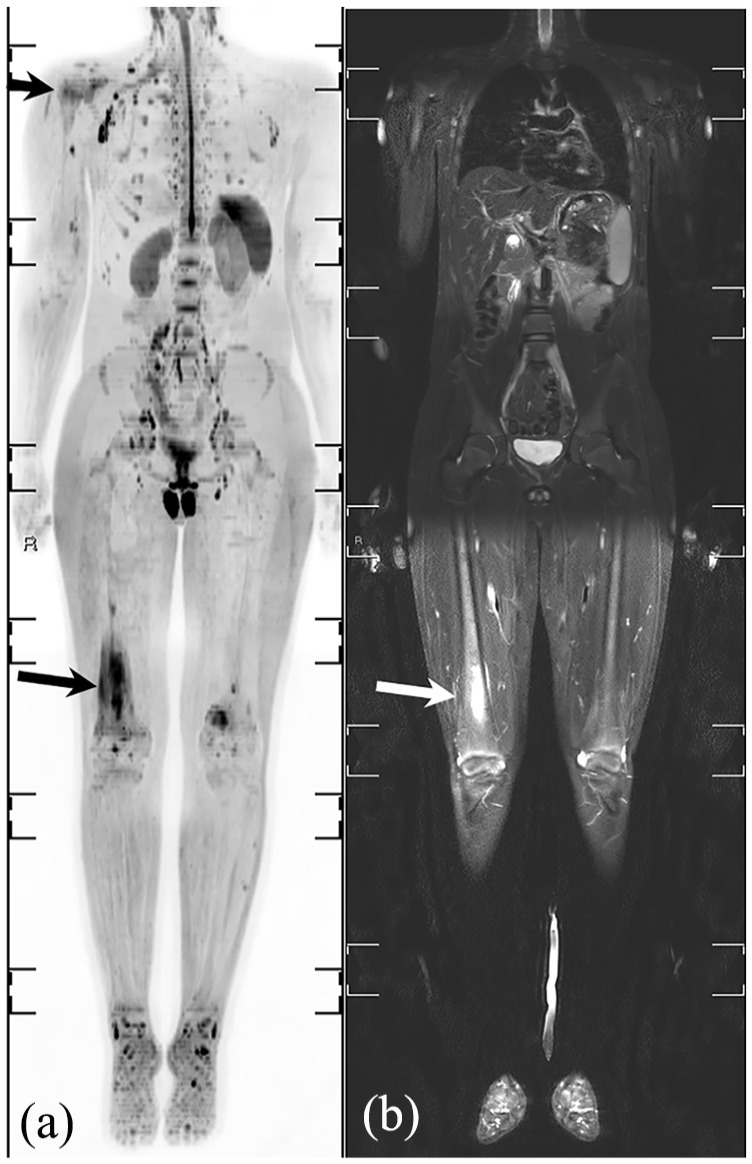

由于技术创新以及对安全和以患者为中心的护理的日益重视,儿童肌肉骨骼成像领域正在取得重大进展。这篇综述探讨了成像方式的最新发展,如先进的磁共振成像、超声创新和人工智能应用。重点包括放射摄影和计算机断层扫描中的辐射剂量降低技术,增强的诊断工具,如对比度增强超声和超高频成像,以及用于病理检测和工作流程优化的人工智能集成。采用先进的方法,如全身磁共振成像和类似计算机断层成像的磁共振成像序列,提高了诊断的准确性,最大限度地减少了辐射暴露,并扩大了非侵入性成像的能力。新兴技术,包括光子计数检测器计算机断层扫描和基于深度学习的重建,正在通过平衡精度和安全性来改变临床实践。人工智能应用正在重塑诊断方法,自动化复杂的评估,并提高效率,尽管外部验证和有限范围等挑战仍然存在。功能成像的进步,如弥散加权成像和正电子发射断层扫描-磁共振成像的整合,正在增强疾病的表征和治疗计划。本综述强调了这些创新的临床影响,强调了标准化方案、跨学科合作和持续研究的必要性,以解决辐射安全和人工智能集成方面未满足的需求。它旨在为医疗保健专业人员提供知识,以利用这些进步改善儿童肌肉骨骼护理的结果。

The field of pediatric musculoskeletal imaging is undergoing significant advancements due to technological innovations and a growing emphasis on safety and patient-centered care. This review explores recent developments in imaging modalities such as advanced magnetic resonance imaging, ultrasound innovations, and artificial intelligence applications. Highlights include radiation dose-reduction techniques in radiography and computed tomography, enhanced diagnostic tools like contrast-enhanced ultrasound and ultra-high-frequency imaging, and the integration of artificial intelligence for pathology detection and workflow optimization. The adoption of advanced methods like whole-body magnetic resonance imaging and computed tomography-like magnetic resonance imaging sequences has improved diagnostic accuracy, minimized radiation exposure, and expanded the capabilities of noninvasive imaging. Emerging technologies, including photon-counting detector computed tomography and deep learning-based reconstructions, are transforming clinical practices by balancing precision and safety. Artificial intelligence applications are reshaping diagnostic approaches, automating complex assessments, and improving efficiency, although challenges such as external validation and limited scope persist. Functional imaging advancements, such as diffusion-weighted imaging and positron emission tomography-magnetic resonance imaging integration, are enhancing disease characterization and treatment planning. This review underscores the clinical impact of these innovations, emphasizing the need for standardized protocols, interdisciplinary collaboration, and continued research to address unmet needs in radiation safety and artificial intelligence integration. It aims to equip healthcare professionals with the knowledge to leverage these advancements for improved outcomes in pediatric musculoskeletal care.